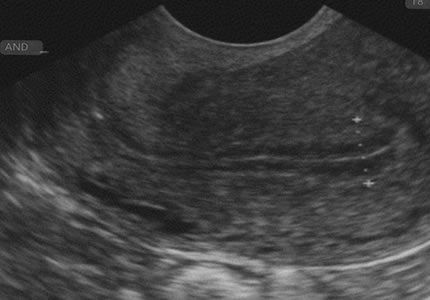

- The success of implantation often depends on the "readiness" of the uterine lining. This scan evaluates the thickness and the "trilaminar" (three-layered) pattern of the endometrium during your mid-to-late cycle. It provides essential data to ensure the environment is optimal for an embryo.

- £140

- Ideal for: IVF and frozen embryo transfer (FET) cycles, donor egg recipients, and luteal-phase monitoring.